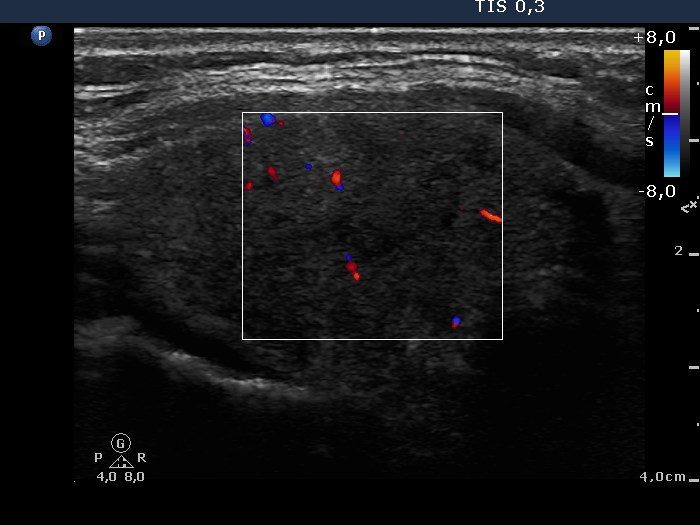

Ultrasonography: There were many hypoechogenic areas with blurred borders within both lobes. The vascularization was decreased.